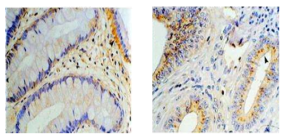

免疫組化實驗

免疫組織化學又稱免疫細胞化學(Immunohistochemistry,IHC),是指帶顯色劑標記的特異性抗體在組織細胞原位通過抗原抗體反應和組織化學的呈色反應,對相應抗原進行定性、定位、定量測定的一項新技術。

它把免疫反應的特異性、組織化學的可見性巧妙地結合起來,借助顯微鏡(包括熒光顯微鏡、電子顯微鏡)的顯像和放大作用,在細胞、亞細胞水平檢測各種抗原物質(如蛋白質、多肽、酶、激素、病原體以及受體等)。

免疫組化是應用免疫學基本原理——抗原抗體反應,即抗原與抗體特異性結合的原理,通過化學反應是標記抗體的顯色劑(熒光素、酶、金屬離子、同位素)顯色來確定組織細胞內抗原(多肽和蛋白質),對其進行定位、定性及定量的研究。